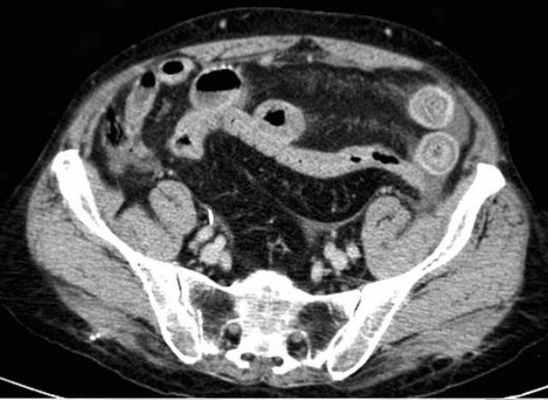

Для странгуляции тонкой кишки характерны утолщение стенок кишечника, васкулярные нарушения и выраженные патологические изменения в брыжейке и в брюшной полости. Диагностические находки включают в себя:

-расширенные петли тонкой кишки проксимальнее транзиторной зоны (зоны обструкции);

-спавшиеся петли кишечника дистальнее уровня обструкции;

-транзиторная зона;

-смешанный характер стаза содержимого кишечника в расширенных петлях с преобладанием жидкостного компонента;

-утолщение стенки кишки циркулярного типа. Важно помнить, такой тип утолщения стенок тонкой кишки при непроходимости как правило связан с сосудистыми нарушениями;

-нарушение нормального контрастного усиления стенок кишки. Изменения варьируют от гиперконтрастирования до полного отсуствия контрастного усиления. Различные варианты этих изменений между описанными выше крайностями могут наблюдаться одновременно в разных сегментах тонкой кишки. Полное отсутствие усиления означает артериальный рефлекторный спазм и свидетельствует в пользу тяжести поражения;

-петля с утолщенными стенками теряет свою эластичность и становится ригидной, вытянутой;

-пристеночный пневматоз тонкой кишки, в особо тяжелых случаях появляются интрамуральные пузырьки газа;

-появление патологических плотностей в брыжейке в виде распространяющихся матовых инфильтратов и тяжистости за счет кровоизлияний в жировые ткани;

-застойные изменения сосудов брыжейки. Сначала диаметр сосудов увеличивается, но со временем наступает рефлекторный артериальный спазм, брыжейка будет выглядеть с обеднённой васкуляризацией. Сосуды сужены или с полностью коллабированным просветом;

-свободная жидкость в карманах брыжейки и в брюшной полости. Иногда жидкость может быть повышенной плотности за счет геморрагического компонента.

примеры странгуляционной осложнённой непроходимости с характерными изменениями в брыжейке, внутрибрюшинном жире, утолщением стенок тонкой кишки и нарушением контрастного усиления.